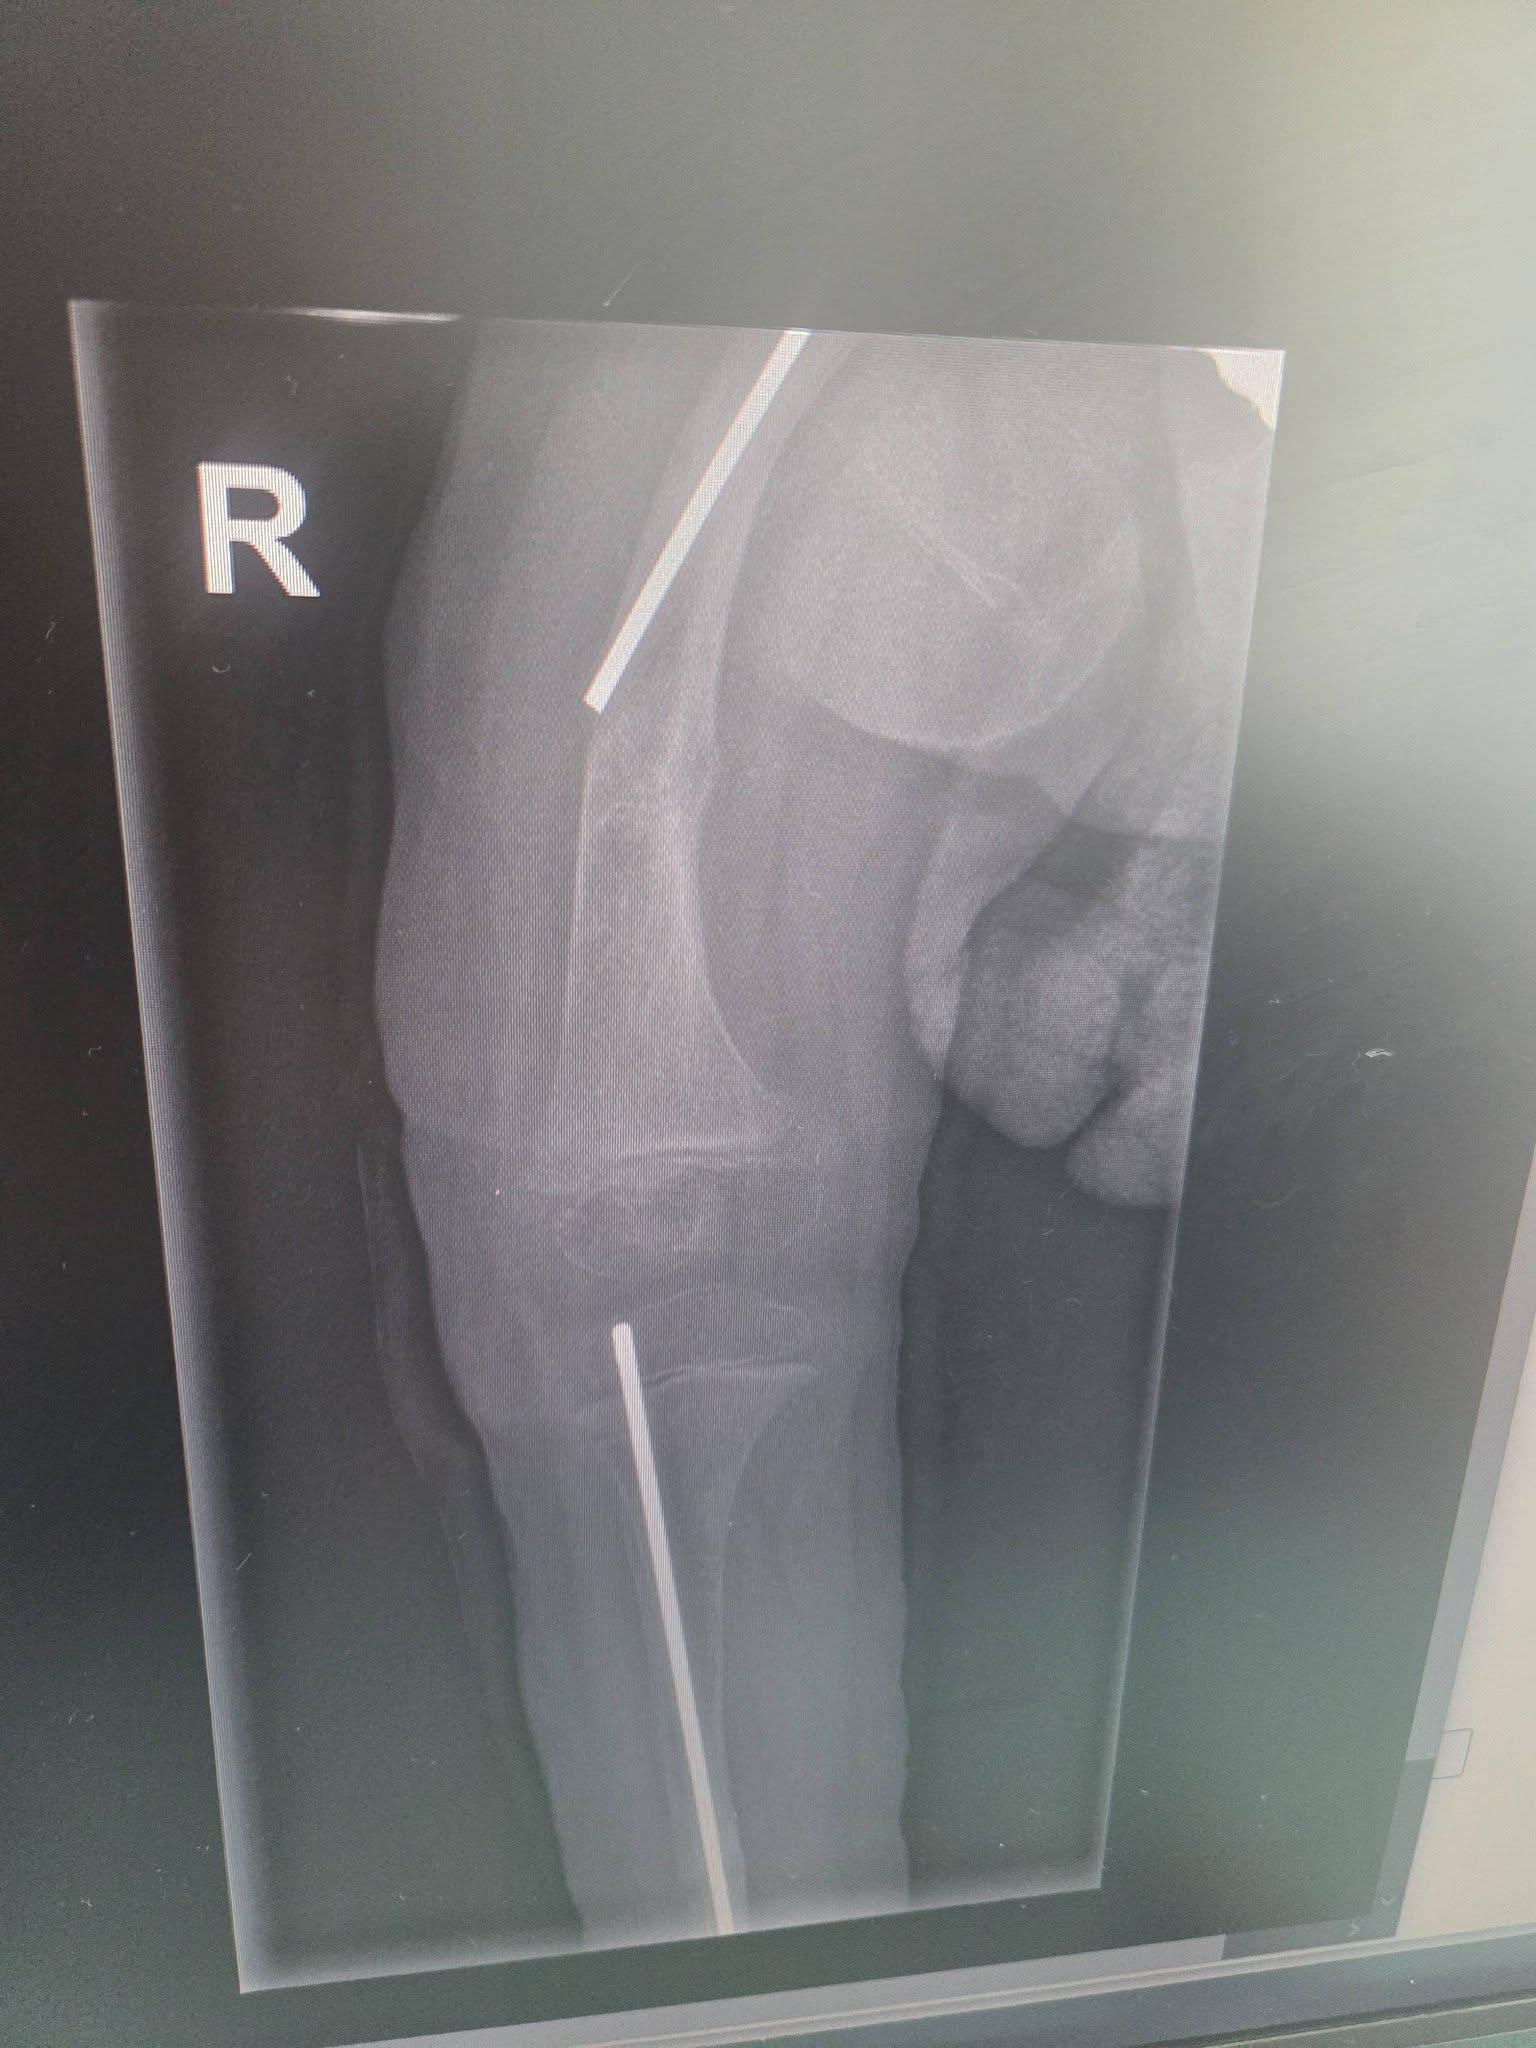

Madzia choruje na wrodzoną łamliwość kości typu III (osteogenesis imperfecta) – rzadką, genetyczną chorobę tkanki łącznej, która powoduje skrajną kruchość kości. Złamań doznała już w życiu płodowym, a jej organizm nie produkuje kolagenu. Choroba jest nieuleczalna, a leczenie ma charakter objawowy i obejmuje stałą rehabilitację, liczne operacje, stabilizację kości oraz specjalistyczną farmakoterapię. Dziewczynka ma za sobą już kilka poważnych zabiegów oraz kilkanaście podań leków wzmacniających kości. Przed nią kolejne operacje i intensywna fizjoterapia, bez której trudno byłoby myśleć o większej samodzielności.